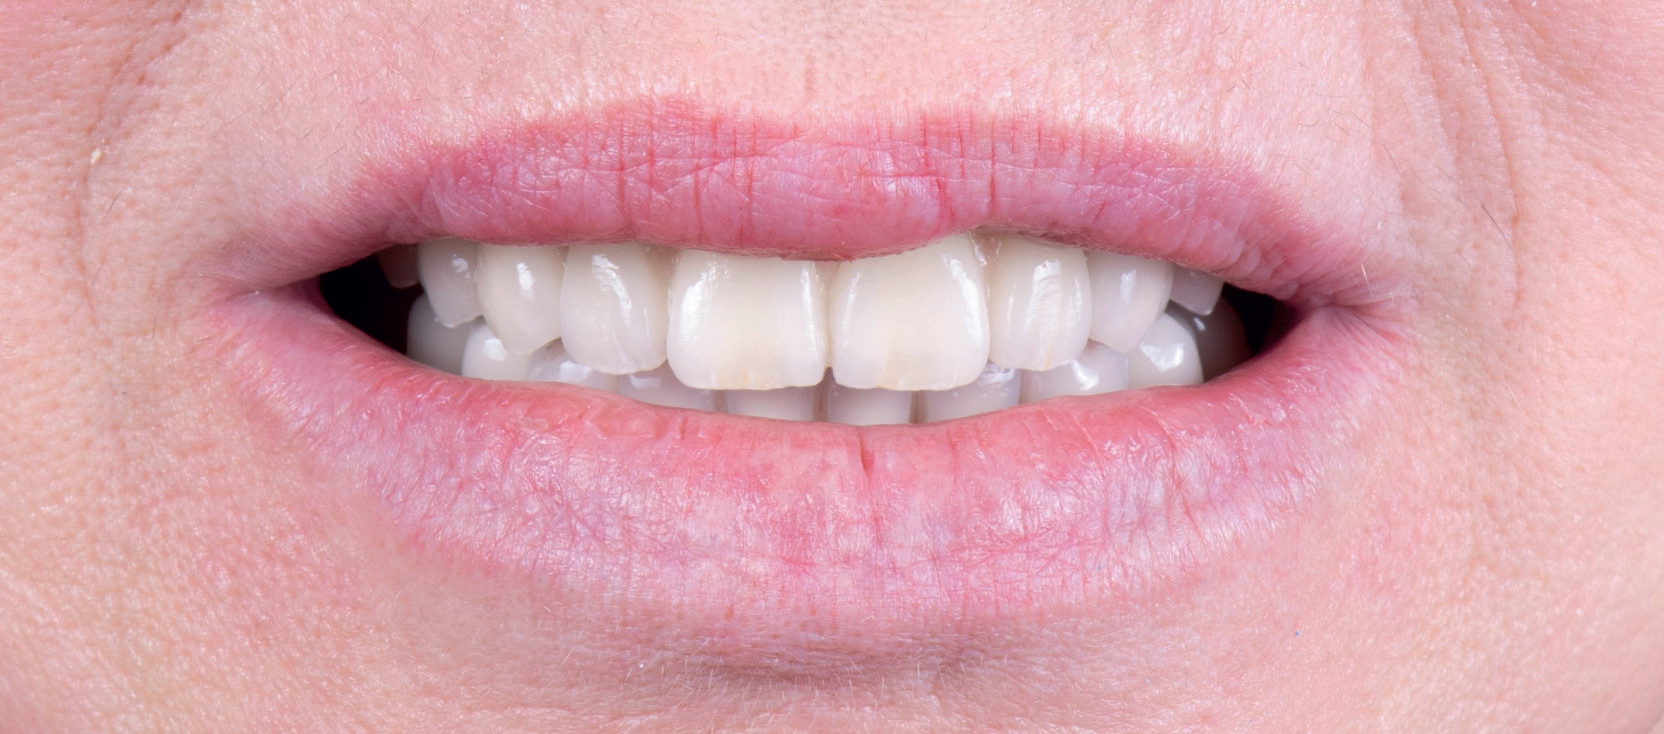

Восстановление утраченного зуба 45 у возрастной пациентки.

✔️ В мягкую кость области зуба 45, удалённого незадолго до обращения, установлен агрессивный корневидный имплант Vega+

✔️ Через 4 месяца проведено протезирование керамической коронкой с трансокклюзионной фиксацией.